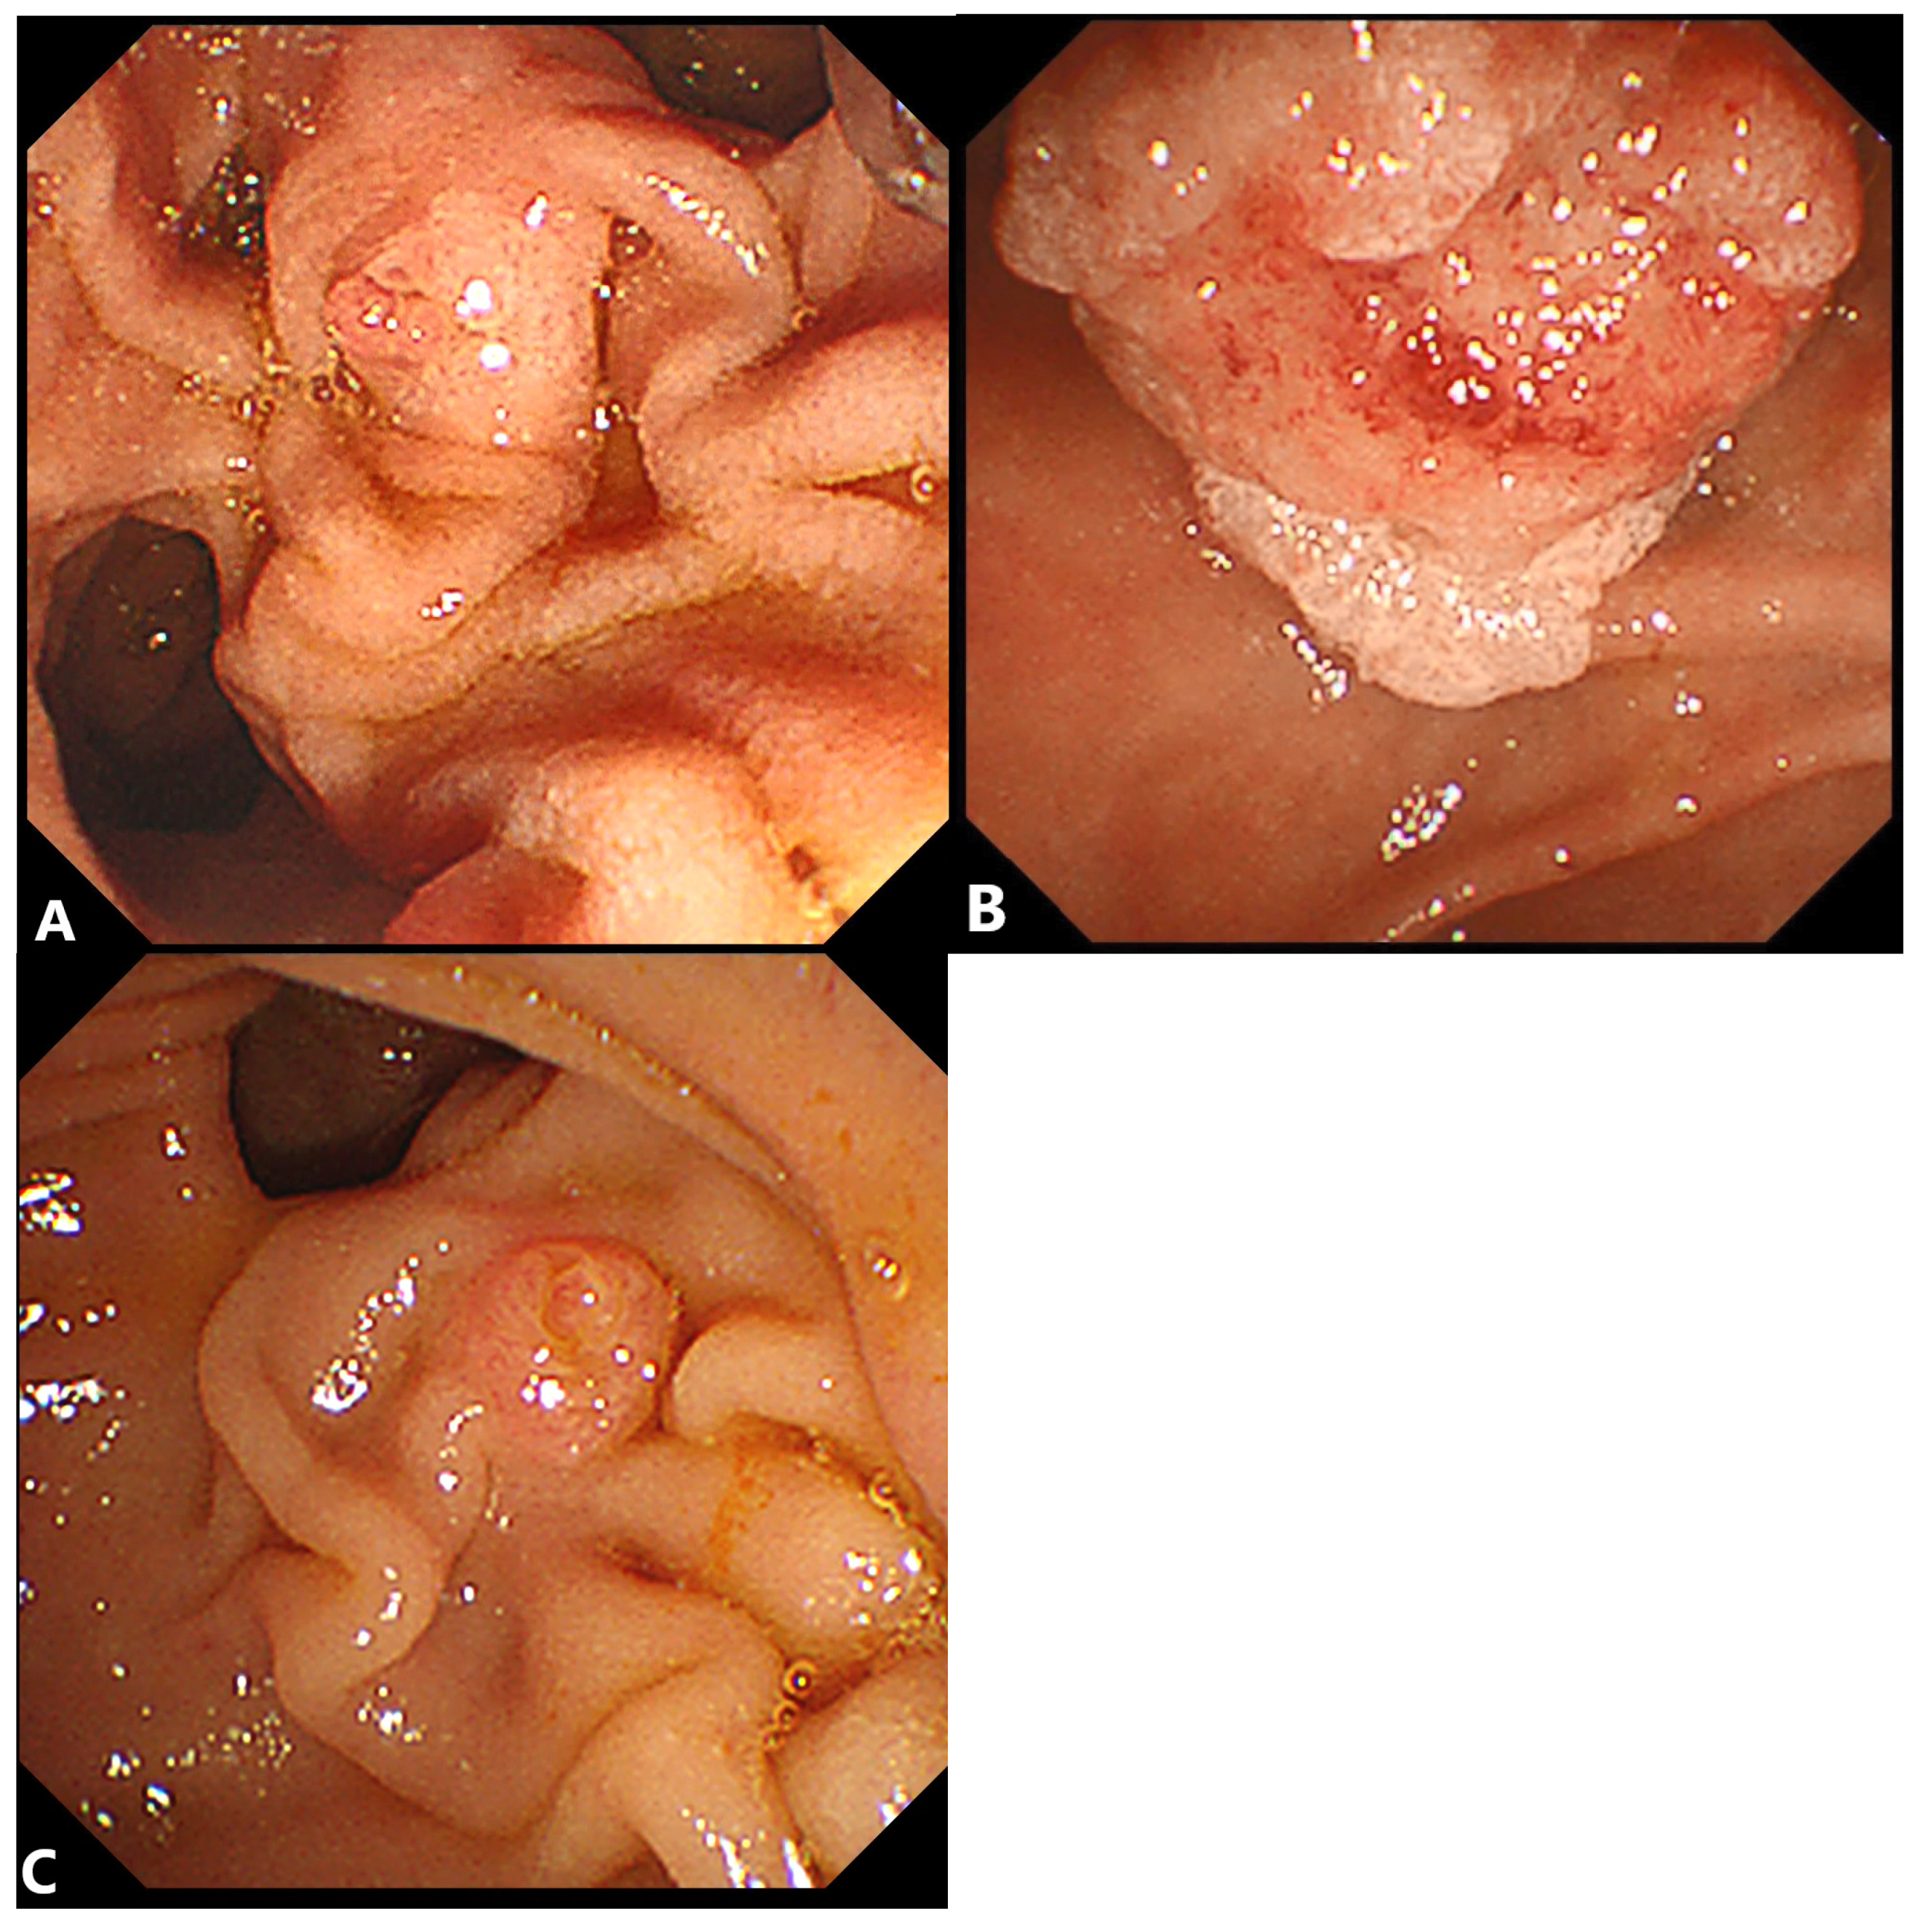

2.2. Precut Papillotomy

2.2.1. Advantages

2.2.2. Disadvantages